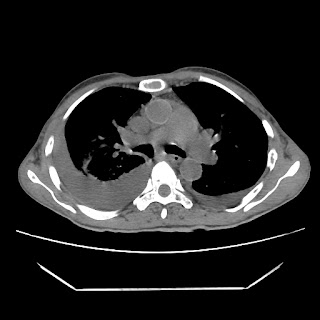

A 56 years old man with

HRCT done on summer season starting 2016